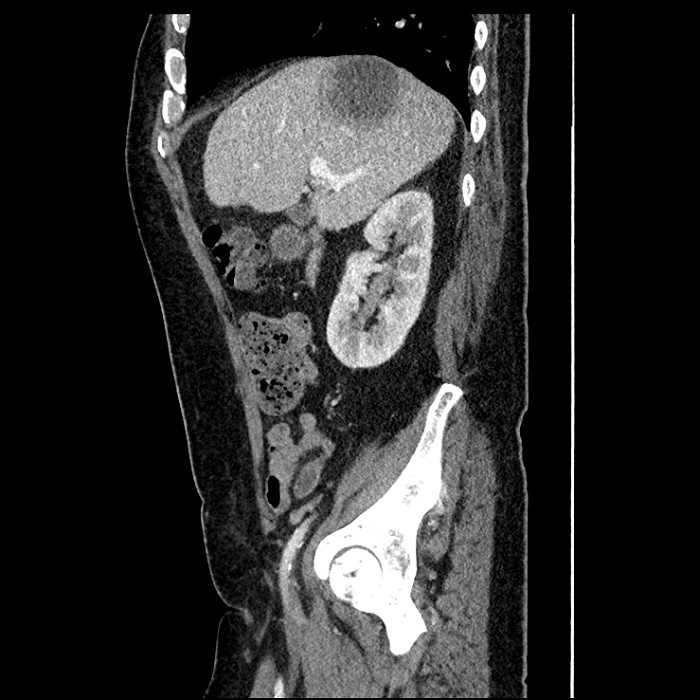

Age: 63

Sex: Male

Indication: Abdominal pain

• Large fluid density structure in hepatic segments 7 and 8 measuring 10 x 7 x 7 cm with internal septation and circumferential ill-defined low density compatible with edema

• Peripherally enhancing subcapsular collections along the anterior margin of the left hepatic lobe measuring 3 x 1 cm and 2 x 1 cm

• Clearly marginated fluid density structure in segment 7 and several other scattered tiny hypodensities, which likely represent cysts

Acute sigmoid diverticulitis complicated by a small contained perforation and a large abscess in the right hepatic lobe. Additional small subcapsular abscesses along the anterior margin of the left hepatic lobe.

• The classic CT imaging appearance is a double target sign with internal low density surrounded by an internal enhancing rim (capsule) and a low density external rim (edema)

Hepatic abscess showing the double target sign with low density internally surrounded by a thin inner enhancing rim (red arrow) and ill-defined outer low density rim (yellow arrow). Blue arrow indicates an internal septation. Red arrows: additional smaller subcapsular abscesses. Red arrow: focal contained perforation associated with diverticulitis.